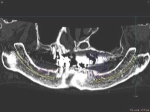

術前術前骨の高さが不足している場合、通常のインプラントでは処置が不可能なものが多い。特殊なショートインプラントを用いて可能になる例。 術前 術前CT像術前CT像術前CT像、下歯槽神経が下あごの中央部を走行しているため利用できる骨の高さが少ない。 埋入予定計画埋入予定計画埋入予定計画 術後レントゲン術後レントゲン、ひだりは少し神経をおそれすぎてやや埋入深度が不足、しかしこれでもしっかりと骨と固着した。